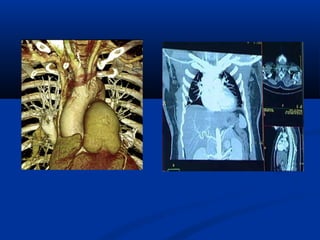

CT ÑA LÔÙP CAÉT (MULTI-SLICE )

-Nhieàu haøng detectors

-Khaûo saùt ñoàng thôøi nhieàu laét

caét

-Thôøi gian queùt nhanh (<0.5

giaây/voøng).

-Khaûo saùt toát trong caùc tröôøng

hôïp caàn thôøi gian nhanh (tim-maïch,

coù bôm caûn quang, boä phaän cöû